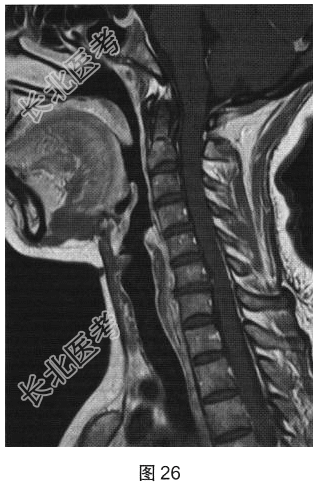

- [材料题] 患者女性,40岁,渐进性肢体无力6个月。颅脑MRI检查如图23、图24所示。

- 简答题1、根据MRI表现,可能的诊断是?